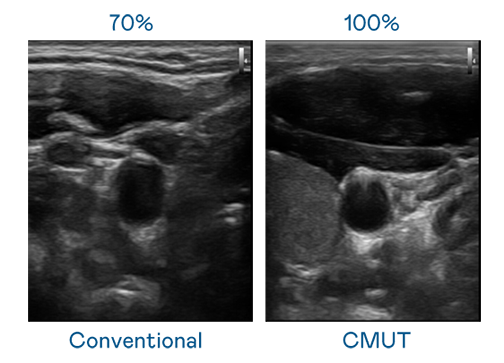

CMUT 技术是一种用电容式微机电元件来产生超音波讯号的技术。与传统 PZT 压电式技术相比,CMUT 频宽增加 30%,更宽频的超音波讯号让影像解析度大幅提升,是实现高影像品质医疗超音波扫描、促进精准医疗发展的关键技术。

大频宽带来超清晰影像

超音波影像的解析度高低,首先取决于探头能发出的讯号频宽。皇冠体育 CMUT 可提供高清晰的超音波讯号,提供高频宽、高灵敏度、影像纹理细节更高的超音波影像,协助医护人员缩短影像判读时间及利用精准的医疗影像进行诊断。